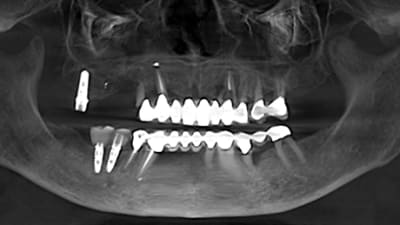

Clinical Technique Review Implantology Osseodensification Effective for Immediate Molar Replacement By Rodrigo Neiva, DDS, Salah Huwais, DDS, Samvel Bleyan, DDS July 15, 2022 13 min read